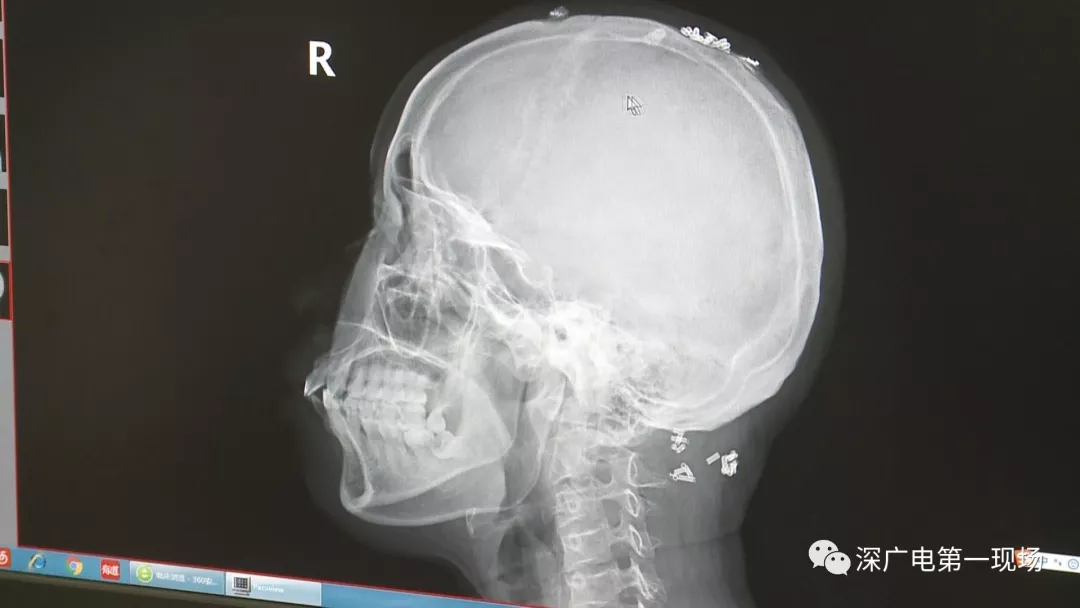

從X光影像圖片中可以看到

患者周身布滿了彈簧圈

深圳大學(xué)總醫(yī)院神經(jīng)外科副主任醫(yī)師陳富勇介紹,當時檢查的時候發(fā)現(xiàn),該患者從頭部到腿部,基本上每個地方都有彈簧,很難數(shù)清具體數(shù)目。